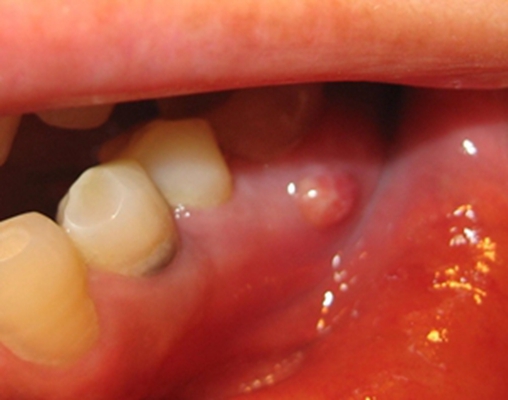

口腔癌圖片

口腔癌的前兆 (6)